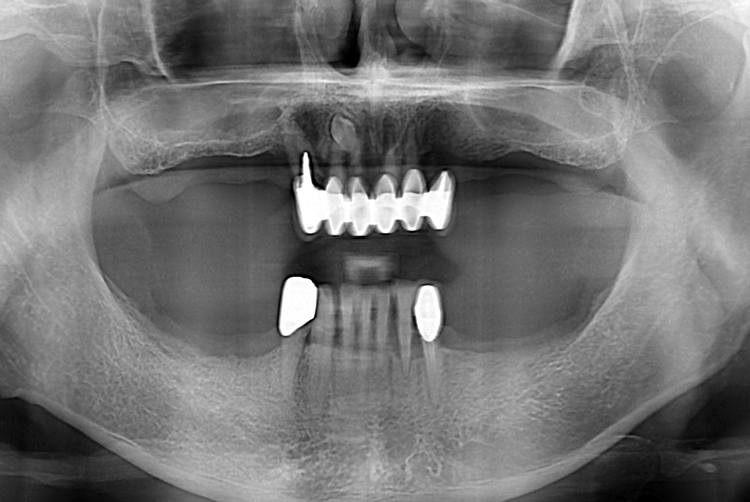

[임플란트] 전체 임플란트

치료전 : 2019-08-02

치료후 : 2019-11-20

세종치과는 많은 환자와 다양한 케이스를 바탕으로

항상 편안한 임플란트 수술을 제공하고자 노력하고,

오래동안 튼튼히 쓸 수 있는 임플란트 수술을 가장 큰 목표로 삼고 있습니다.